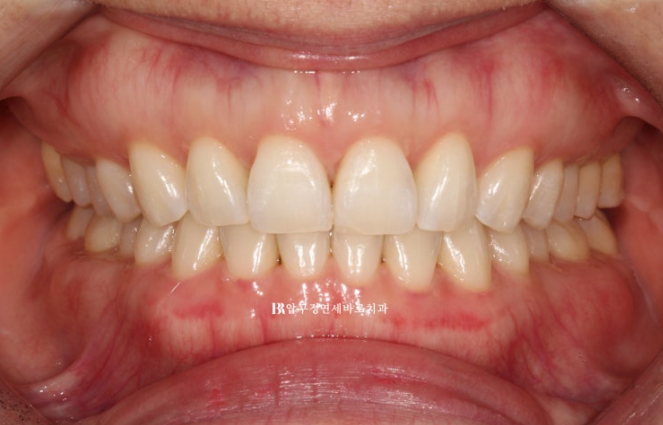

23년 7월부터 23년 12월까지 약 5개월에 걸쳐서 1차 세트 장치 14개를 다 착용한 후 모습입니다.

23.12

가위교합과 벌어졌던 공간은 이미 해결이 되었습니다.

중심선도 잘 맞습니다.